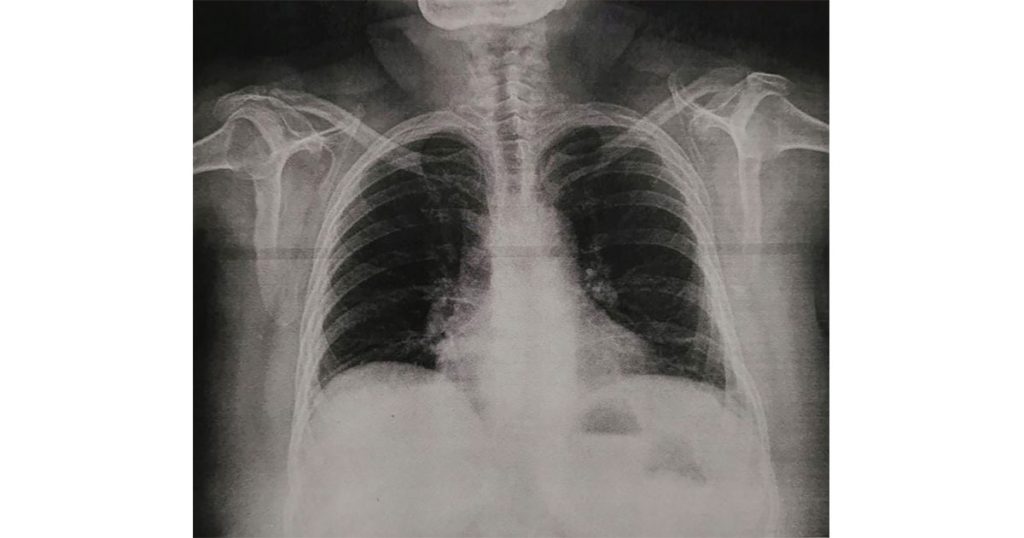

En el marco del Día Mundial sin Tabaco, el titular del instituto aseguró que este hábito representa una afectación severa en la población, su consumo puede provocar enfermedades pulmonares obstructivas crónicas, las cuales son una de las primeras 15 causas de mortalidad hospitalaria en el Issste, como consta en el Anuario Estadístico 2021 bit.ly/3wWo8Js. Por ello, la dependencia mantiene el objetivo de orientar, sensibilizar y apoyar a los pacientes a modificar prácticas que dañen su salud.

La jefa de departamento del Programa de Salud Mental, Lucía Ledesma Torres, puntualizó que el consumo de tabaco es un factor de riesgo importante que provoca enfermedades como: bronquitis crónica, enfisema pulmonar, cáncer de pulmón, hipertensión arterial, infarto del miocardio, accidentes cerebrovasculares, úlcera gastrointestinal, gastritis crónica, ansiedad e insomnio, entre otras. “Quienes las presentan tienen mayor riesgo de desarrollar síntomas graves en caso de ser infectadas por COVID-19”.

Señaló que incluso incrementa la gravedad de patologías respiratorias como el asma y dificulta su control, aún con medicamentos. “El tabaco irrita las vías respiratorias, provocando inflamación, las cuales se estrechan y se llenan de mucosidad pegajosa, condiciones que favorecen el ataque de este padecimiento”.